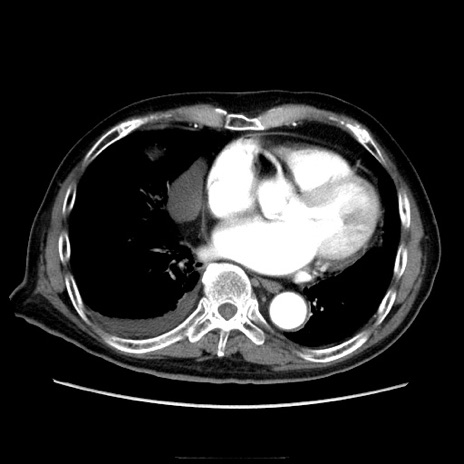

症例21(横断像)

【症例】70歳代男性

【主訴】腹痛

【現病歴】肝硬変・肝細胞癌にてかかりつけの方。約9時間前に食後より腹痛出現。症状が徐々に増悪し、嘔吐出現したため来院。

【既往歴】肝硬変、肝細胞癌(RFA、TACE後)

【身体所見】意識清明、表情苦悶様、BT 36℃、BP 129/78mmHg、P 88bpm、SpO2 97%(RA)、右上腹部から心窩部にかけて圧痛あり、反跳痛なし、筋性防御あり。

【データ】WBC 5800、CRP 0.16